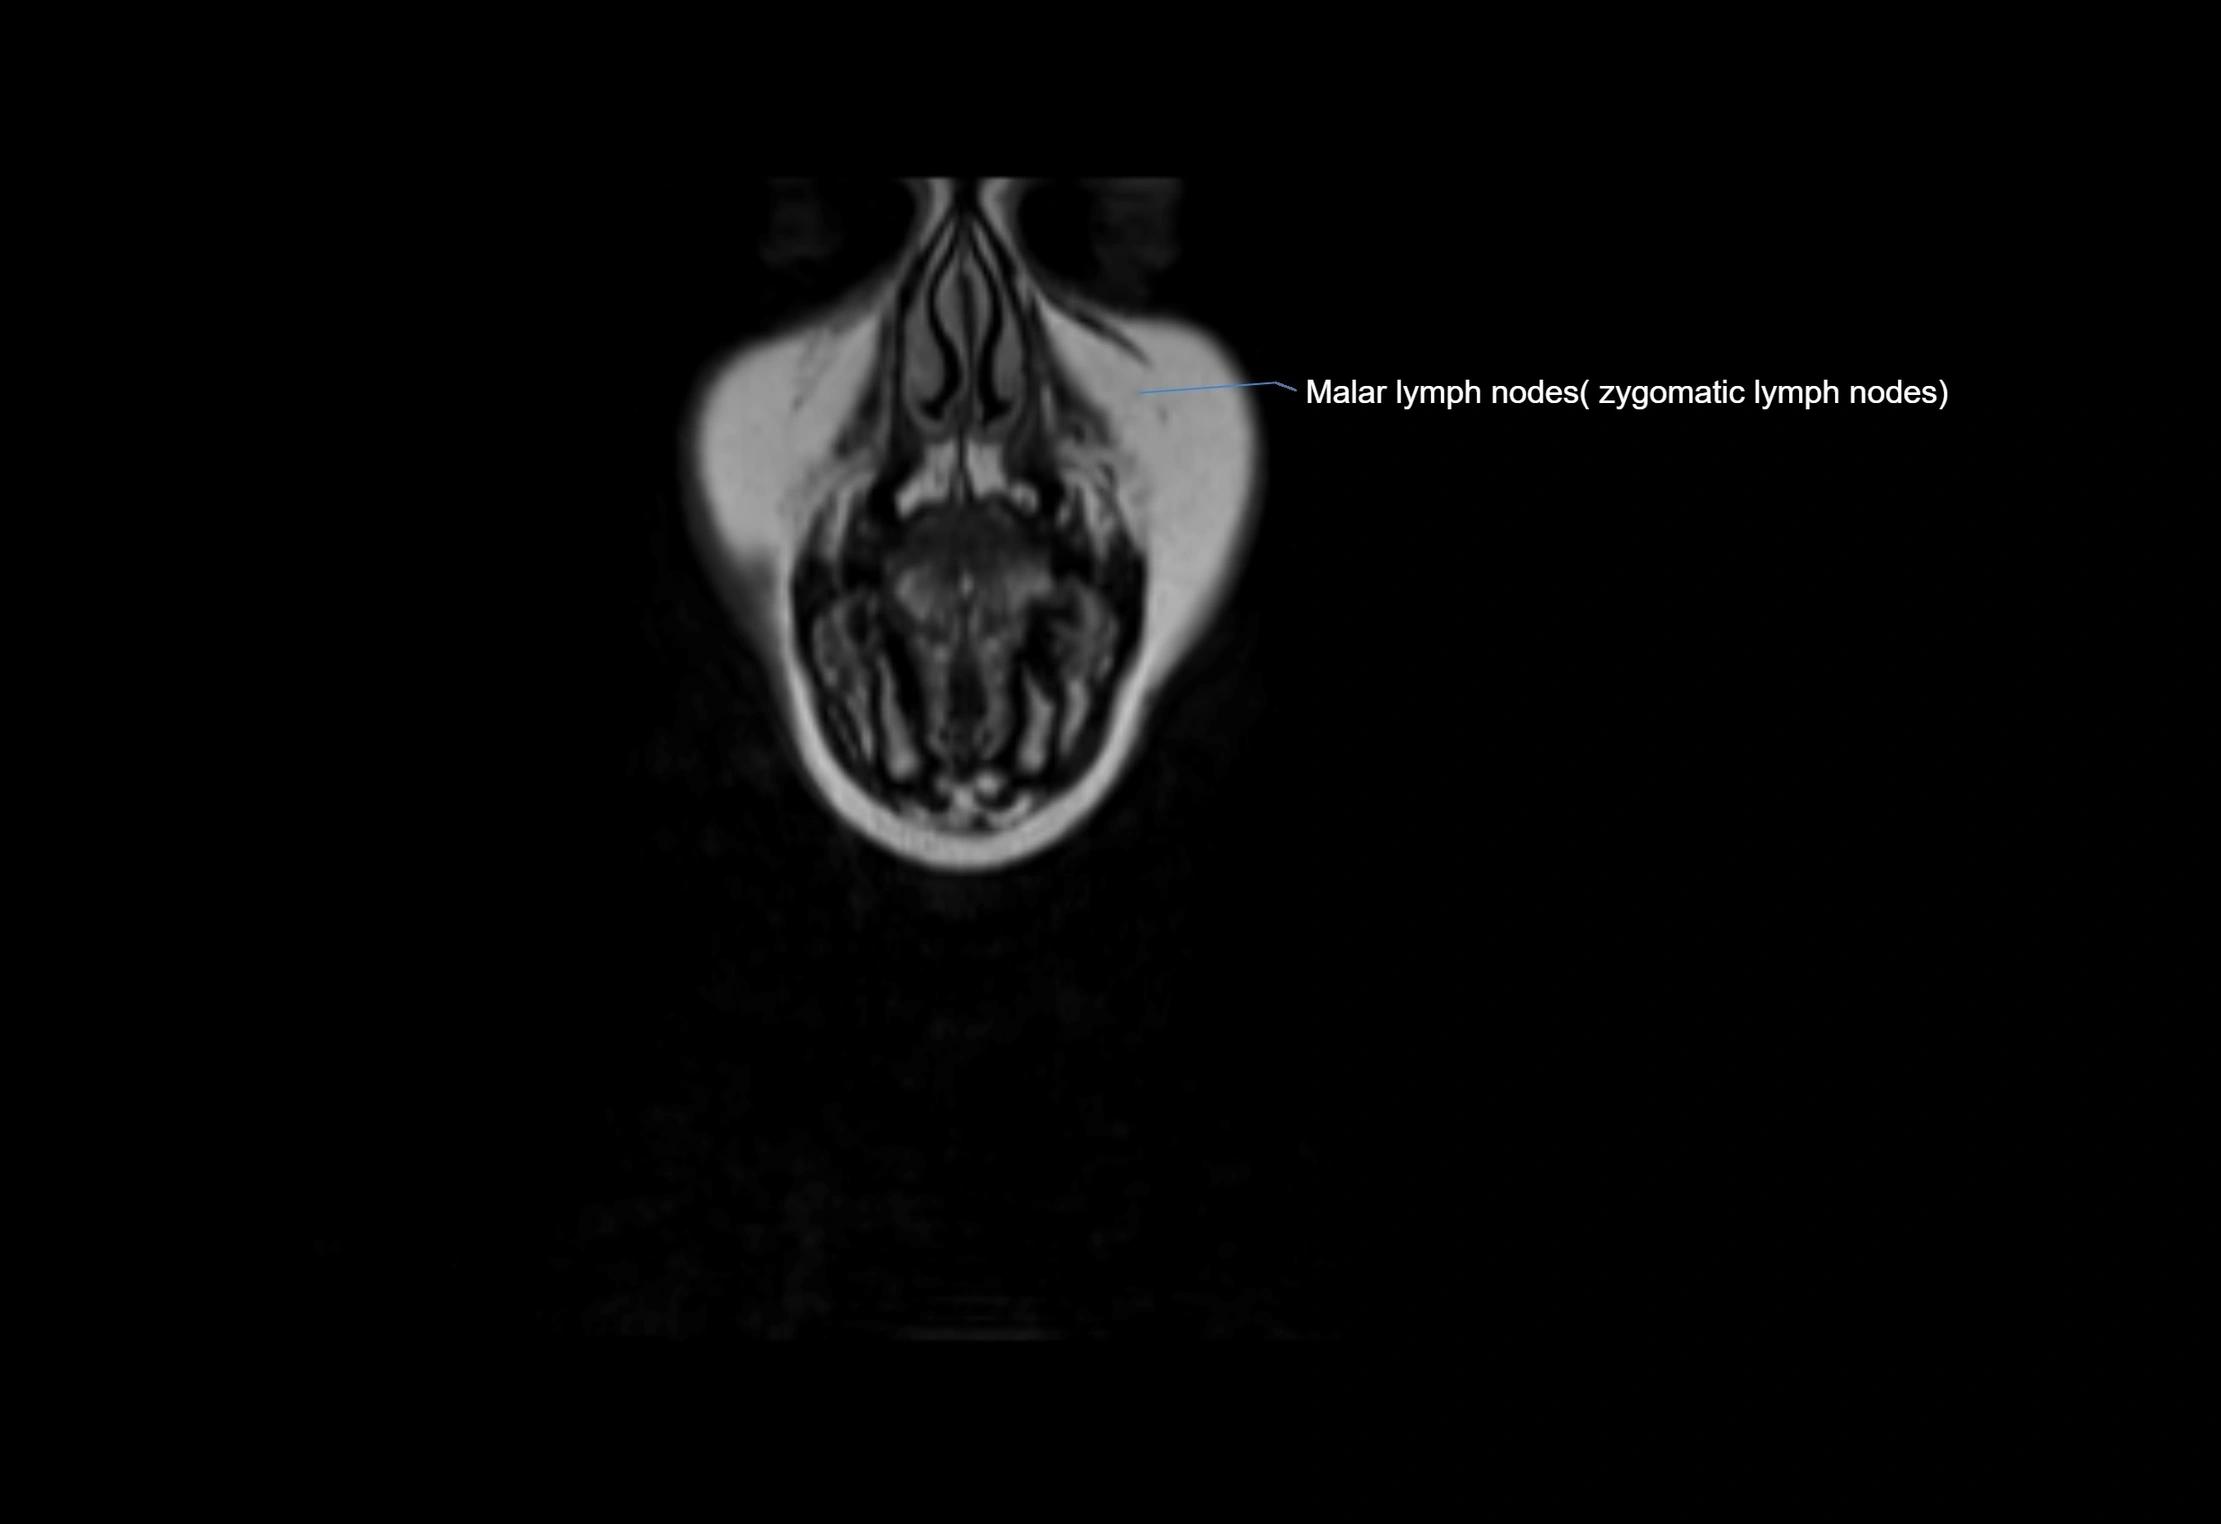

MRI images

image